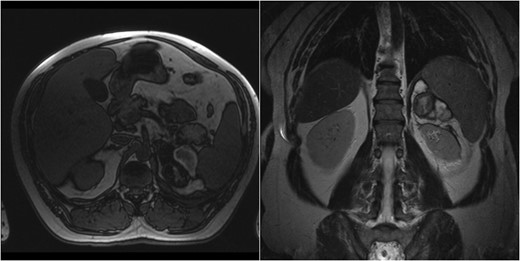

A 60-year-old male presented with pain at the left upper quadrant and left flank, radiating to the back. The patient had known hypertension and had suffered a myocardial infarction a year ago with stent insertion, now being on aspirin and clopidogrel. Upon admission all observations were normal. On examination, tenderness with guarding were noted at the left upper quadrant. Giordano sign was strongly elicited. Laboratory investigations were normal other than leukocytosis (WBC: 15.300, 89% neutrophils). US was unremarkable and CT scan revealed a retroperitoneal hematoma, at the site of the left adrenal gland, associated with extravasation of contrast (Fig. 3). The patient underwent angiography and active bleeding was confirmed from the middle adrenal artery which was successfully embolized microspheres (Fig. 4). The patient was transferred to ICU. He remained hemodynamically stable, without requiring blood transfusion. Four days later he was transferred to the ward. Pheochromocytoma was excluded with VMA, while ACTH and cortisol measurements ruled out adrenal insufficiency. Clopidogrel was permanently discontinued. The patient was discharged after 14 days and follow-up MRI confirmed hematoma resolution excluding an underlying mass.

Case 2 presenting imaging (CT) showing a large left peri-adrenal hematoma.